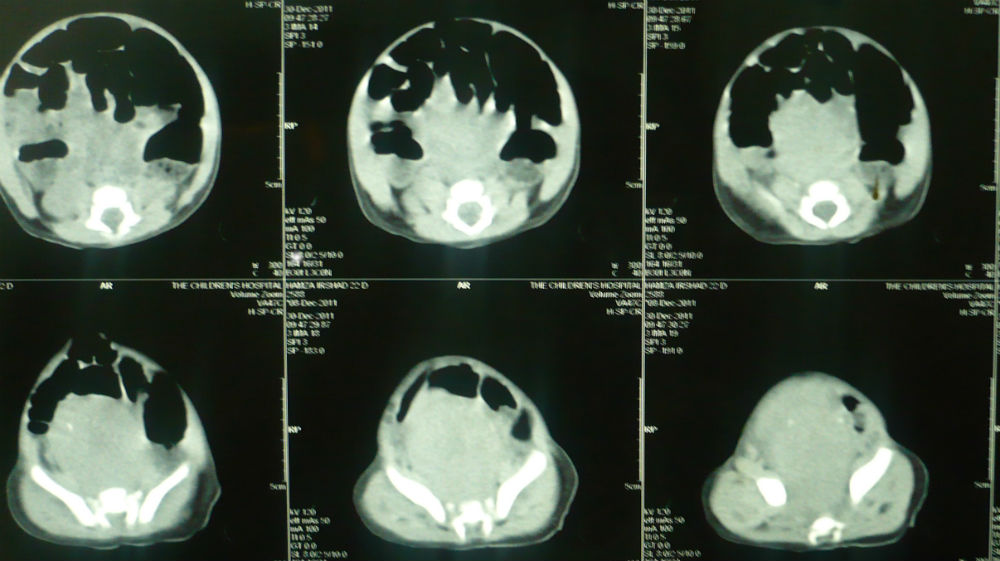

In some cases with calcifications in the mass, the differentials are further converged to sacrococcygeal teratoma and rarely presacral neuroblastoma.[4.5] Problem arises when AFP is inconclusive of SCT. Raveenthiran [5] called SCT as great masquerader. However, sometimes the inverse may be true. We had a 25-days-old male baby presented with constipation and a palpable mass in the pelvis. Ultrasound and CT scan showed calcifications in the mass. The CT scan opinion was type-IV SCT (Fig. 2). The patient was explored from lower abdominal incision. The mass was dissected retro-rectally and surprisingly entire mass was excised in-toto attached to a nerve fiber (Fig. 3). It was decided to postpone the coccygectomy till the biopsy confirmation as the mass was firm (less suspicious of SCT in setting of normal AFP) and attached to a nerve. Biopsy was suggestive of neuroblastoma.

Figure 2: A presacral mass with calcifications. |